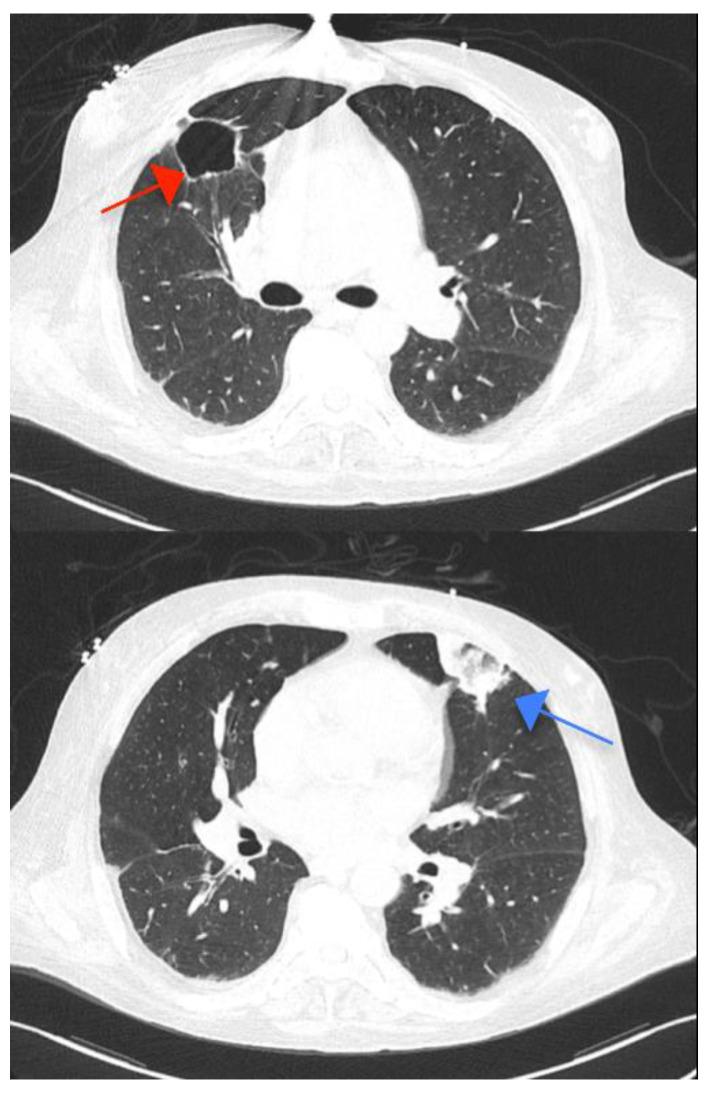

is a rare yet particularly aggressive infective endocarditis pathogen. We describe a case of successfully managed double-valve infective endocarditis, in which the presumed source of bacteremia was a long-term tunneled central venous catheter used for hemodialysis.

是一种罕见但特别侵袭性的感染性心内膜炎病原体。我们描述了一例成功治疗的双瓣膜感染性心内膜炎病例,该病例菌血症的疑似来源是用于血液透析的长期隧道式中心静脉导管。